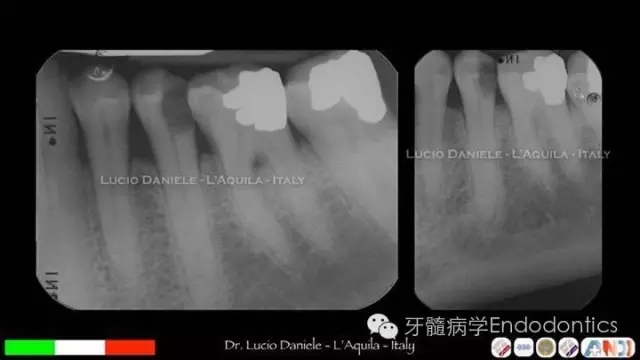

圖1. MTA直接蓋髓

圖2.